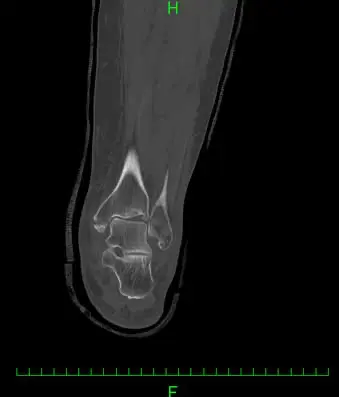

(図2)CT

足関節内外果骨折、脛骨天蓋部に5mmのstep offを伴う陥没骨折と踵骨アキレス腱付着部より1.5cm近位に骨片を認める。